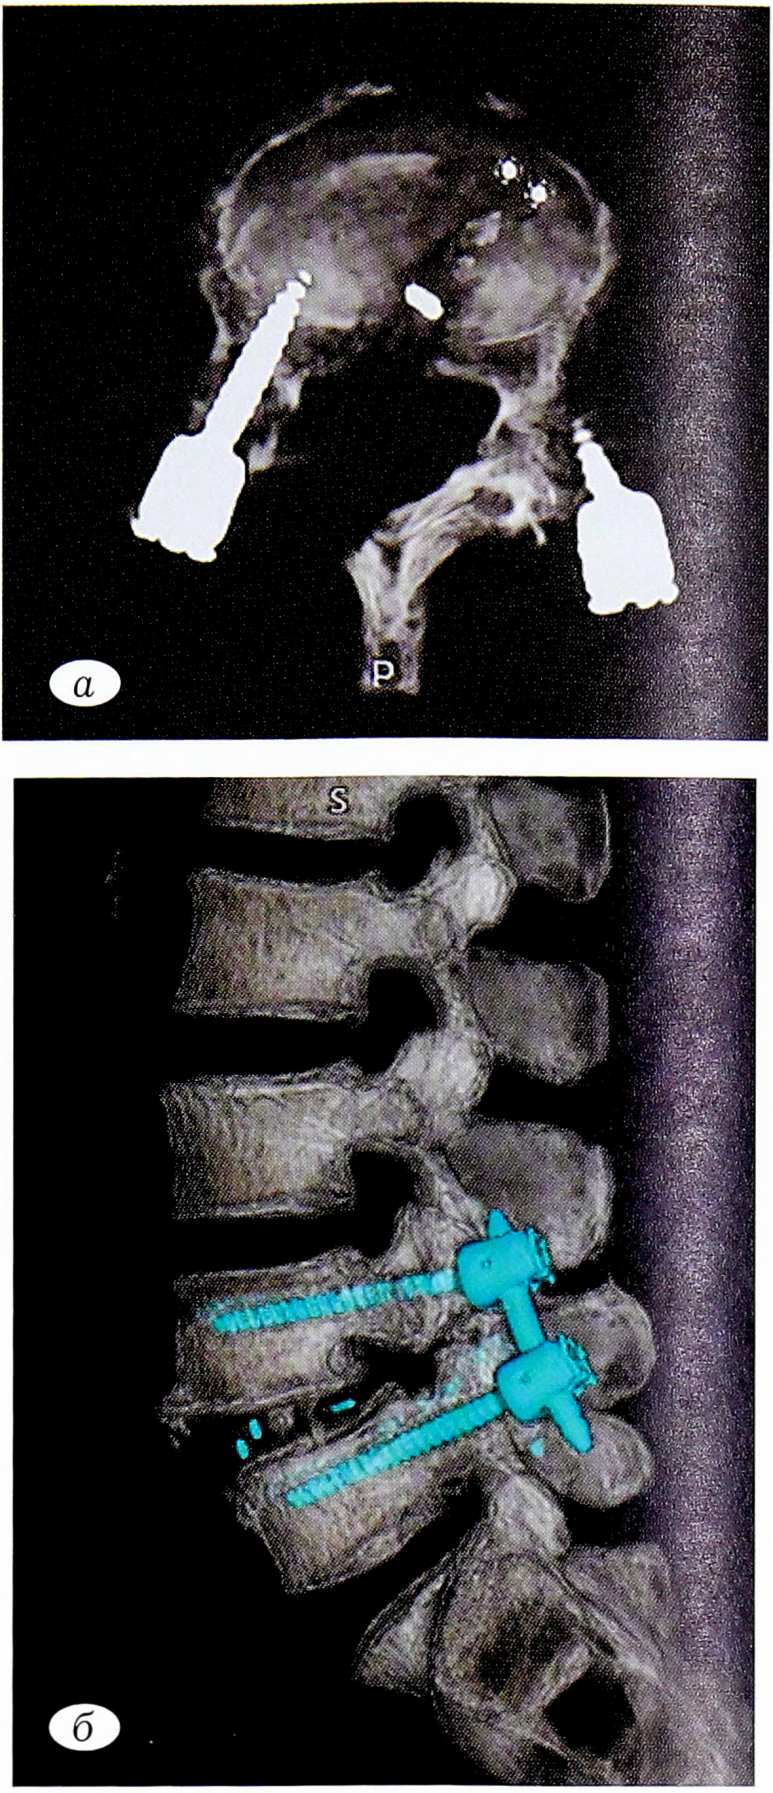

По данным мультиспиральной компьютерной томографии (МСКТ) поясничного отдела позвоночника с 3D-реконструкцией, произведенной через 6 мес в плановом порядке (рис. 6): состояние после межтелового спондилодеза с транспедикулярной фиксацией в сегменте LIV-LV, формирующийся костный блок II стадии по Bridwell.

Рис. 6. Послеоперационная картина MCKT поясничного отдела позвоночника с 3D-реконструкцией: а — аксиальная проекция на уровне межтелового пространства LIV-LV; б — 3D-реконструкция поясничного отдела позвоночника.

Fig. 6. Postoperative MSCT picture of the lumbar spine with 3D reconstruction: a — axial projection at the level of the interbody space LIV-LV; b — 3D reconstruction of the lumbar spine.